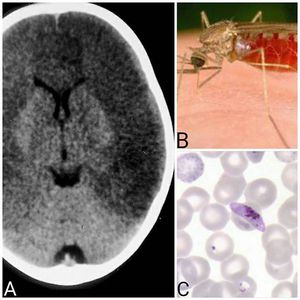

Malaria is an infection caused by protoza plasmodium. There are 4 species of plasmodium, falciparum, vivax, ovale, and malariae. Transmission is by Anopheles mosquito(Figure.B).»Symptoms of malaria are:-1.Cyclic fever at 48-72 hour intervals with chills.2.Hemolytic anemia(Figure.C)3.Splenomegaly (After 4 days of symptoms)4.Hyperventilation5.Agitation5.Bleeding»Complications of malaria are:-1.Cerebral malaria(Figure.A)2.Renal failure 3.Acute tubular necrosis4.Noncardiogenic pulmonary edema»Treatment of malaria is:-1.Cholorquine2.Primaquine3.IV Quinidine: For severe infections